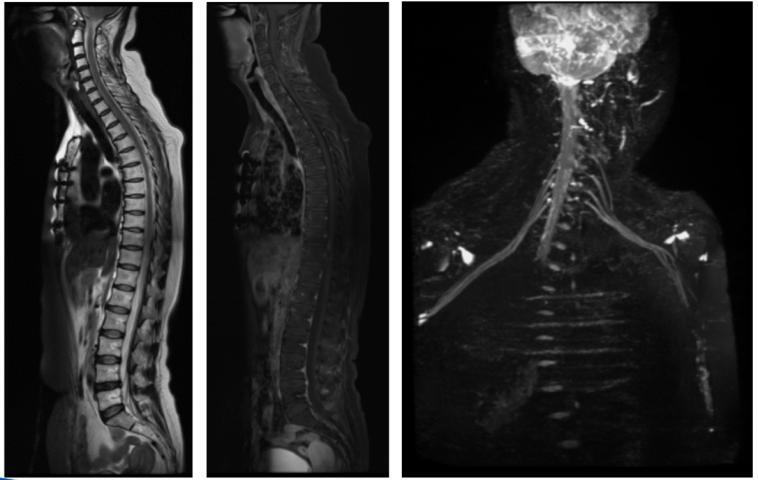

神经系统-全脊柱成像,臂丛神经成像

颈椎成像,使用CoilShim后,压脂不均匀区域的压脂效果明显改善。